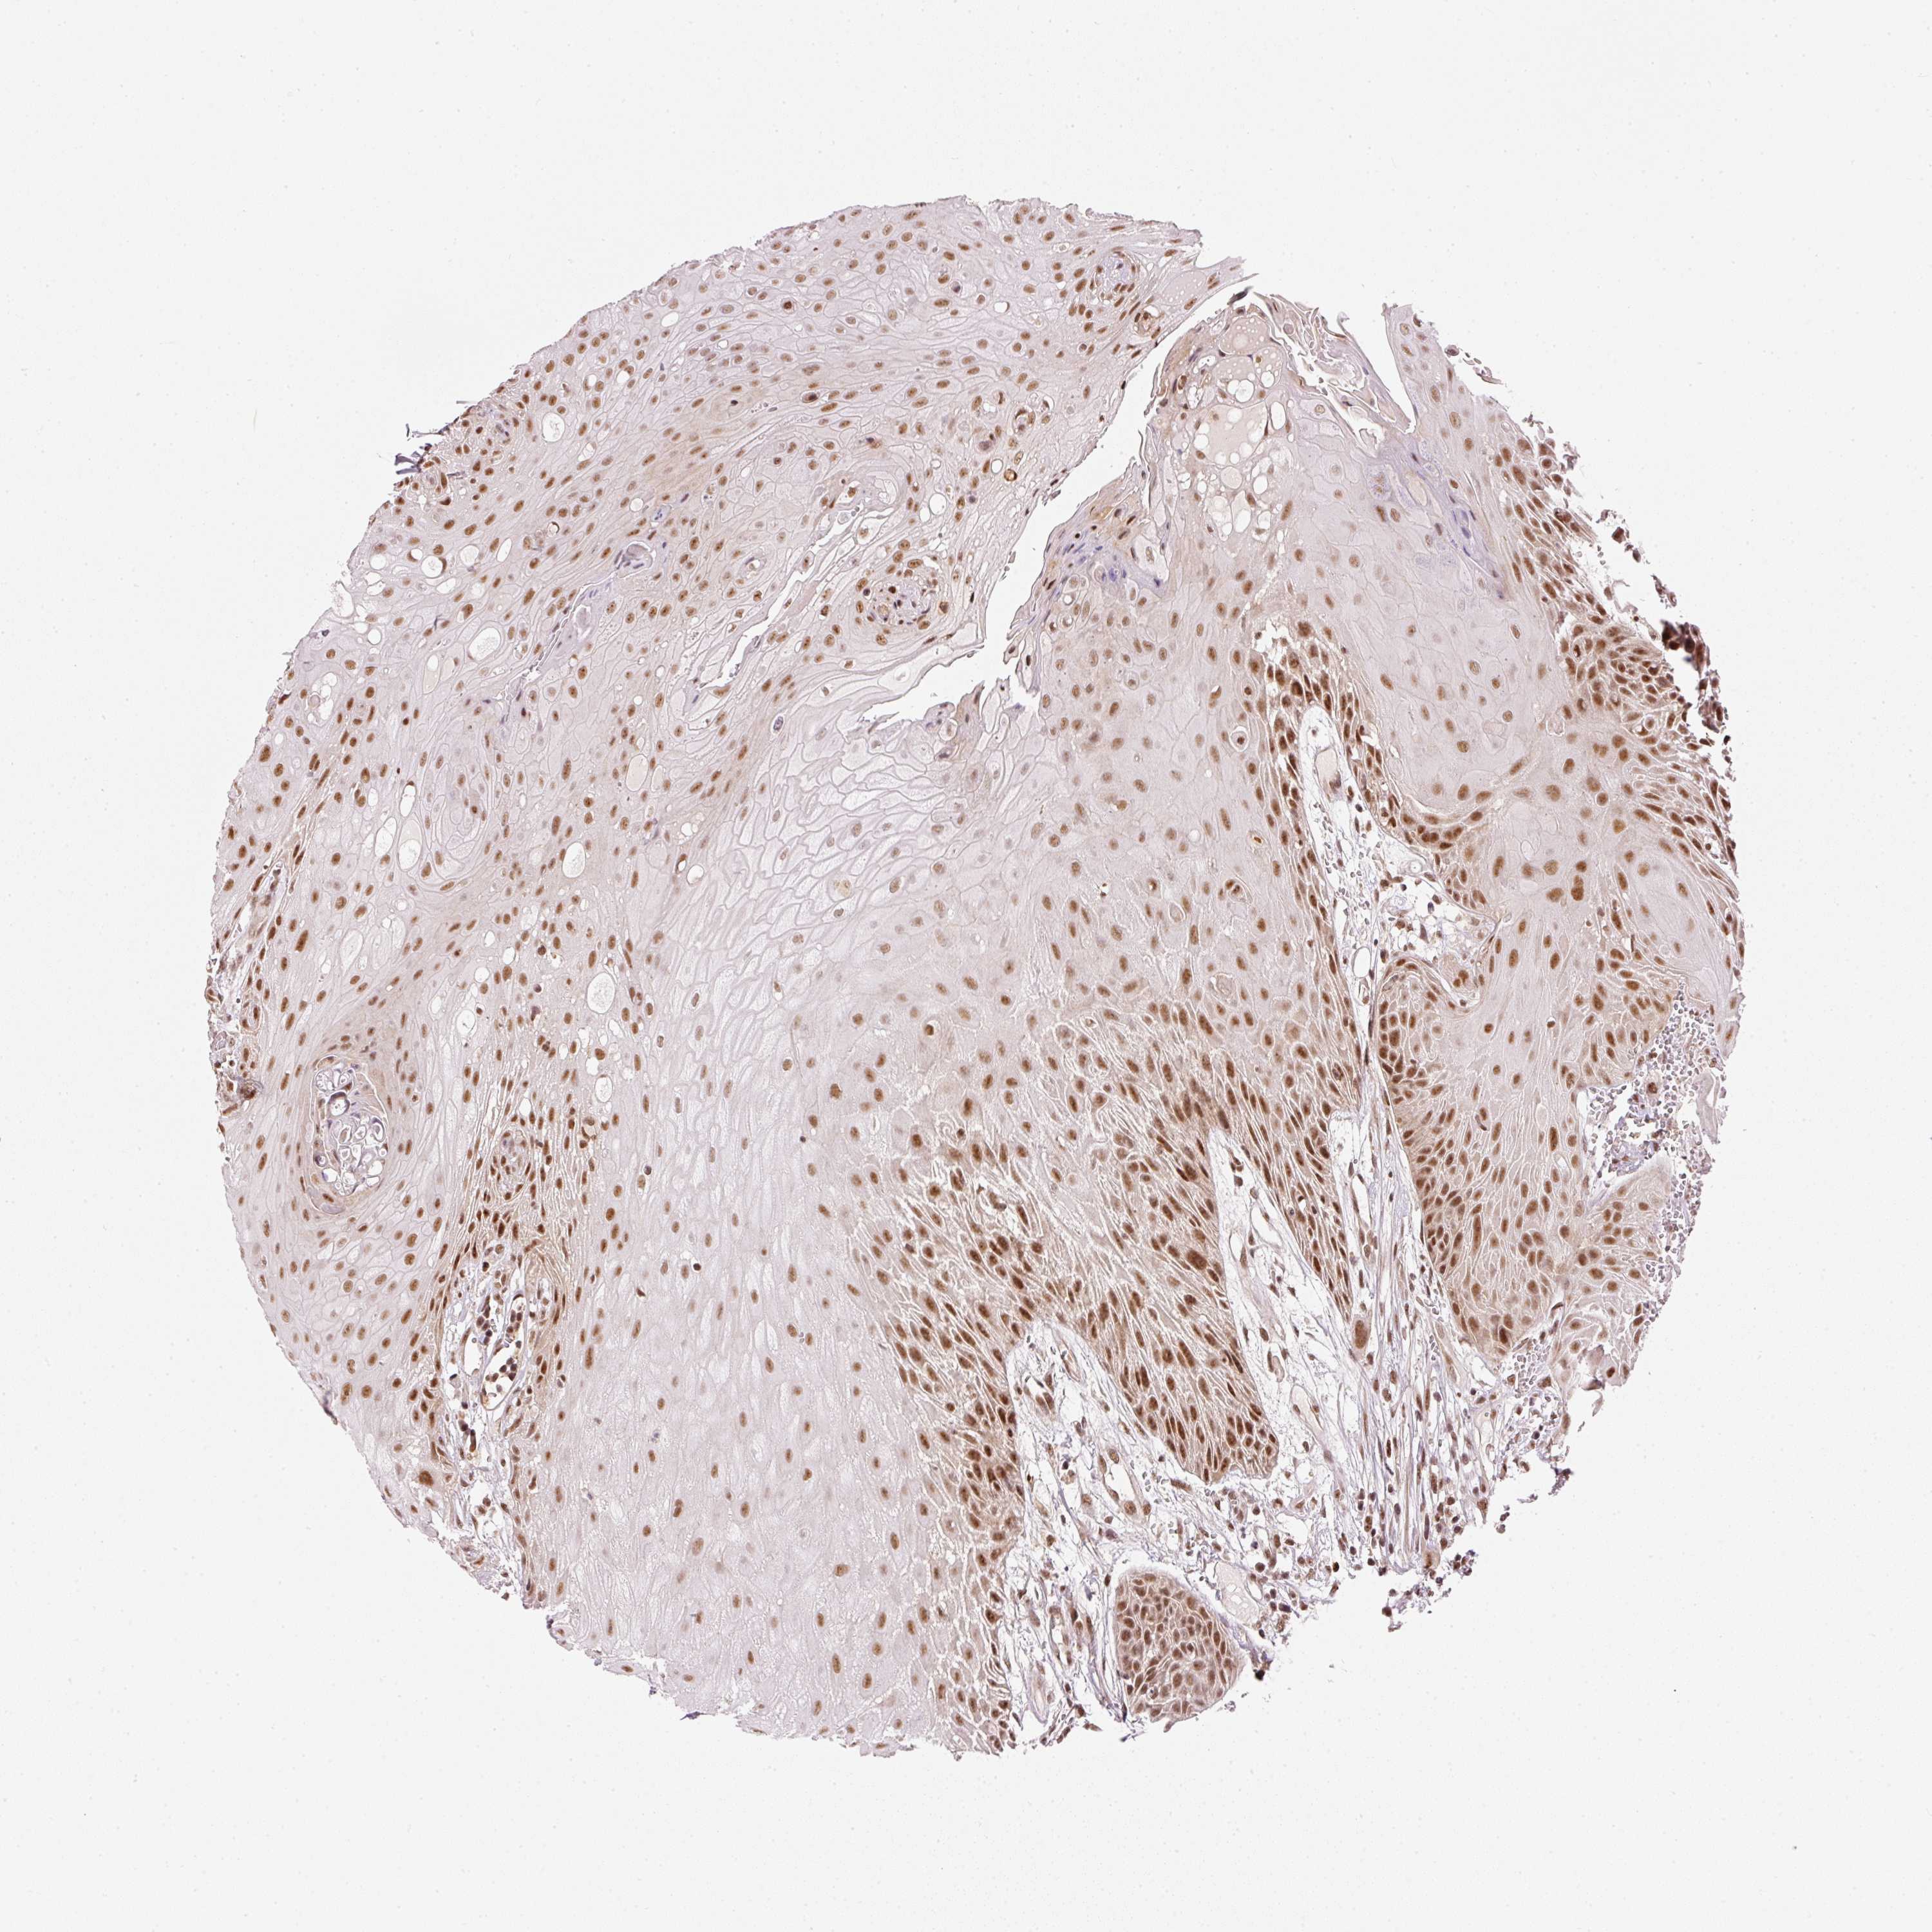

HEAD AND NECK CANCER - Protein expressioni

A mouse-over function shows sample information and annotation data. Click on an image to view it in a full screen mode. Samples can be filtered based on level of antibody staining by selecting one or several of the following categories: high, medium, low and not detected. The assay and annotation is described here.

Antibody stainingi

Antibody staining in the annotated cell types in the current human tissue is reported as not detected, low, medium, or high, based on conventional immunohistochemistry profiling in selected tissues. This score is based on the combination of the staining intensity and fraction of stained cells.

Each image is clickable and will lead to virtual microscopy that enables deeper exploration of all samples and also displays staining intensity scores, fraction scores and subcellular localization as well as patient and tissue information for each sample.

Antibody HPA052953

Staining

High

Medium

Low

Not detected

Intensity

Strong

Moderate

Weak

Negative

Quantity

>75%

75%-25%

<25%

None

Location

Nuclear

Cytoplasmic/membranous

Cytoplasmic/membranous,nuclear

Squamous cell carcinoma, NOS